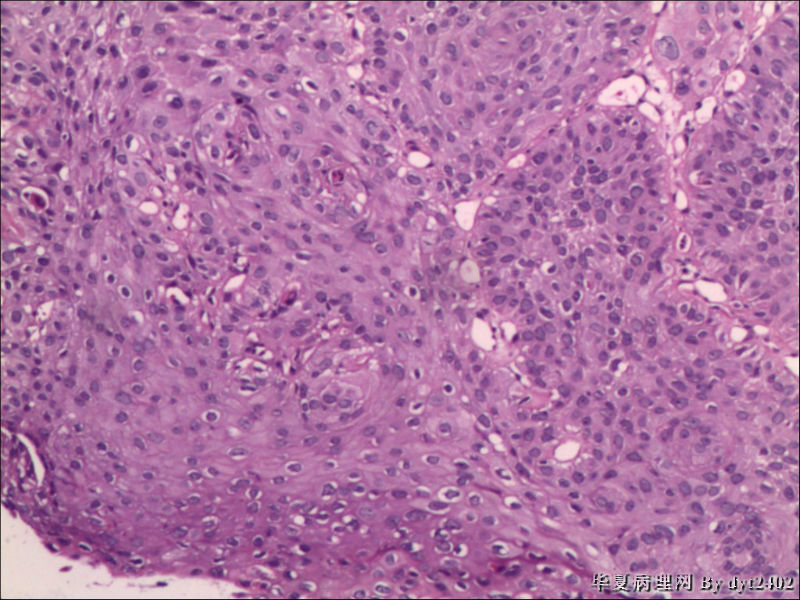

这样的外阴病变 发个原位癌是否合适?

• 这样的外阴病变 发个原位癌是否合适?图3

图3

原位癌够了,不排除其他地方有浸润。

似乎有浸润了

VIN III,做个银染或者标个免疫组化看一下基底膜是否完整。

看上去好像还完整 只是经常看见图5 那样结构的就觉得可能还有更重病变

VIN III